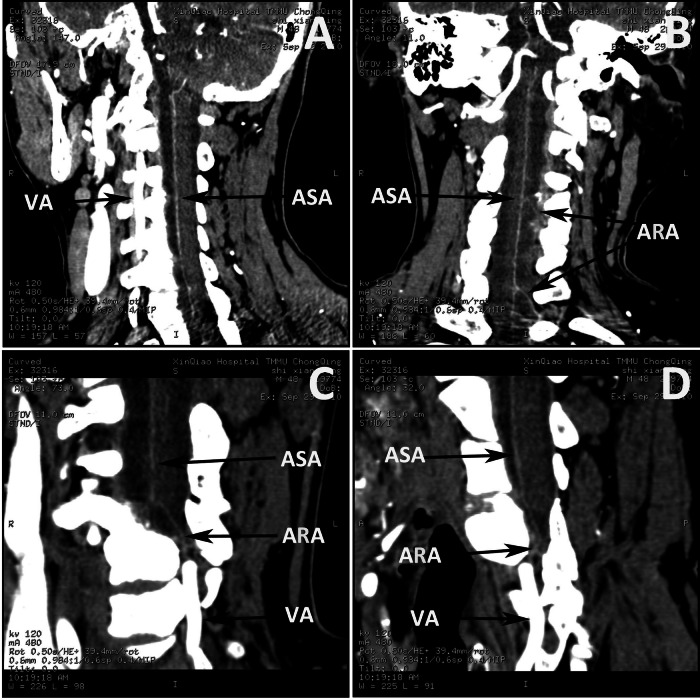

The ASA was identified by maintaining the maximum intensity projection slab parallel to the anterior surface of the spinal cord at each vertebral level assessed from C1 to C7. An enhanced artery on the midline ventral surface of the spinal cord was interpreted as the ASA (Fig. 1A). At the same time, an artery originating from the VA and coursing through the intervertebral foramen to join the ASA in a hairpin configuration was interpreted as the ARA. Covisualization of the ASA and the ARA was used to identify the ASA (Fig. 1B); the covisualization of veins was not a criterion for identifying the ASA. Another criterion was that the ASA originated from the VA in the skull base (Fig. 1C, D). Interrater reliability, in the form of the consensual identification of the ASA by two radiologists, was required.

Fig. 1. Identification of the ASA, ARA and VA.

Coronal (A), sagittal (B), and oblique-sagittal (C, D) CTA views showing the ASA, and ARA and VA (arrows) as the suppliers of the ASA.